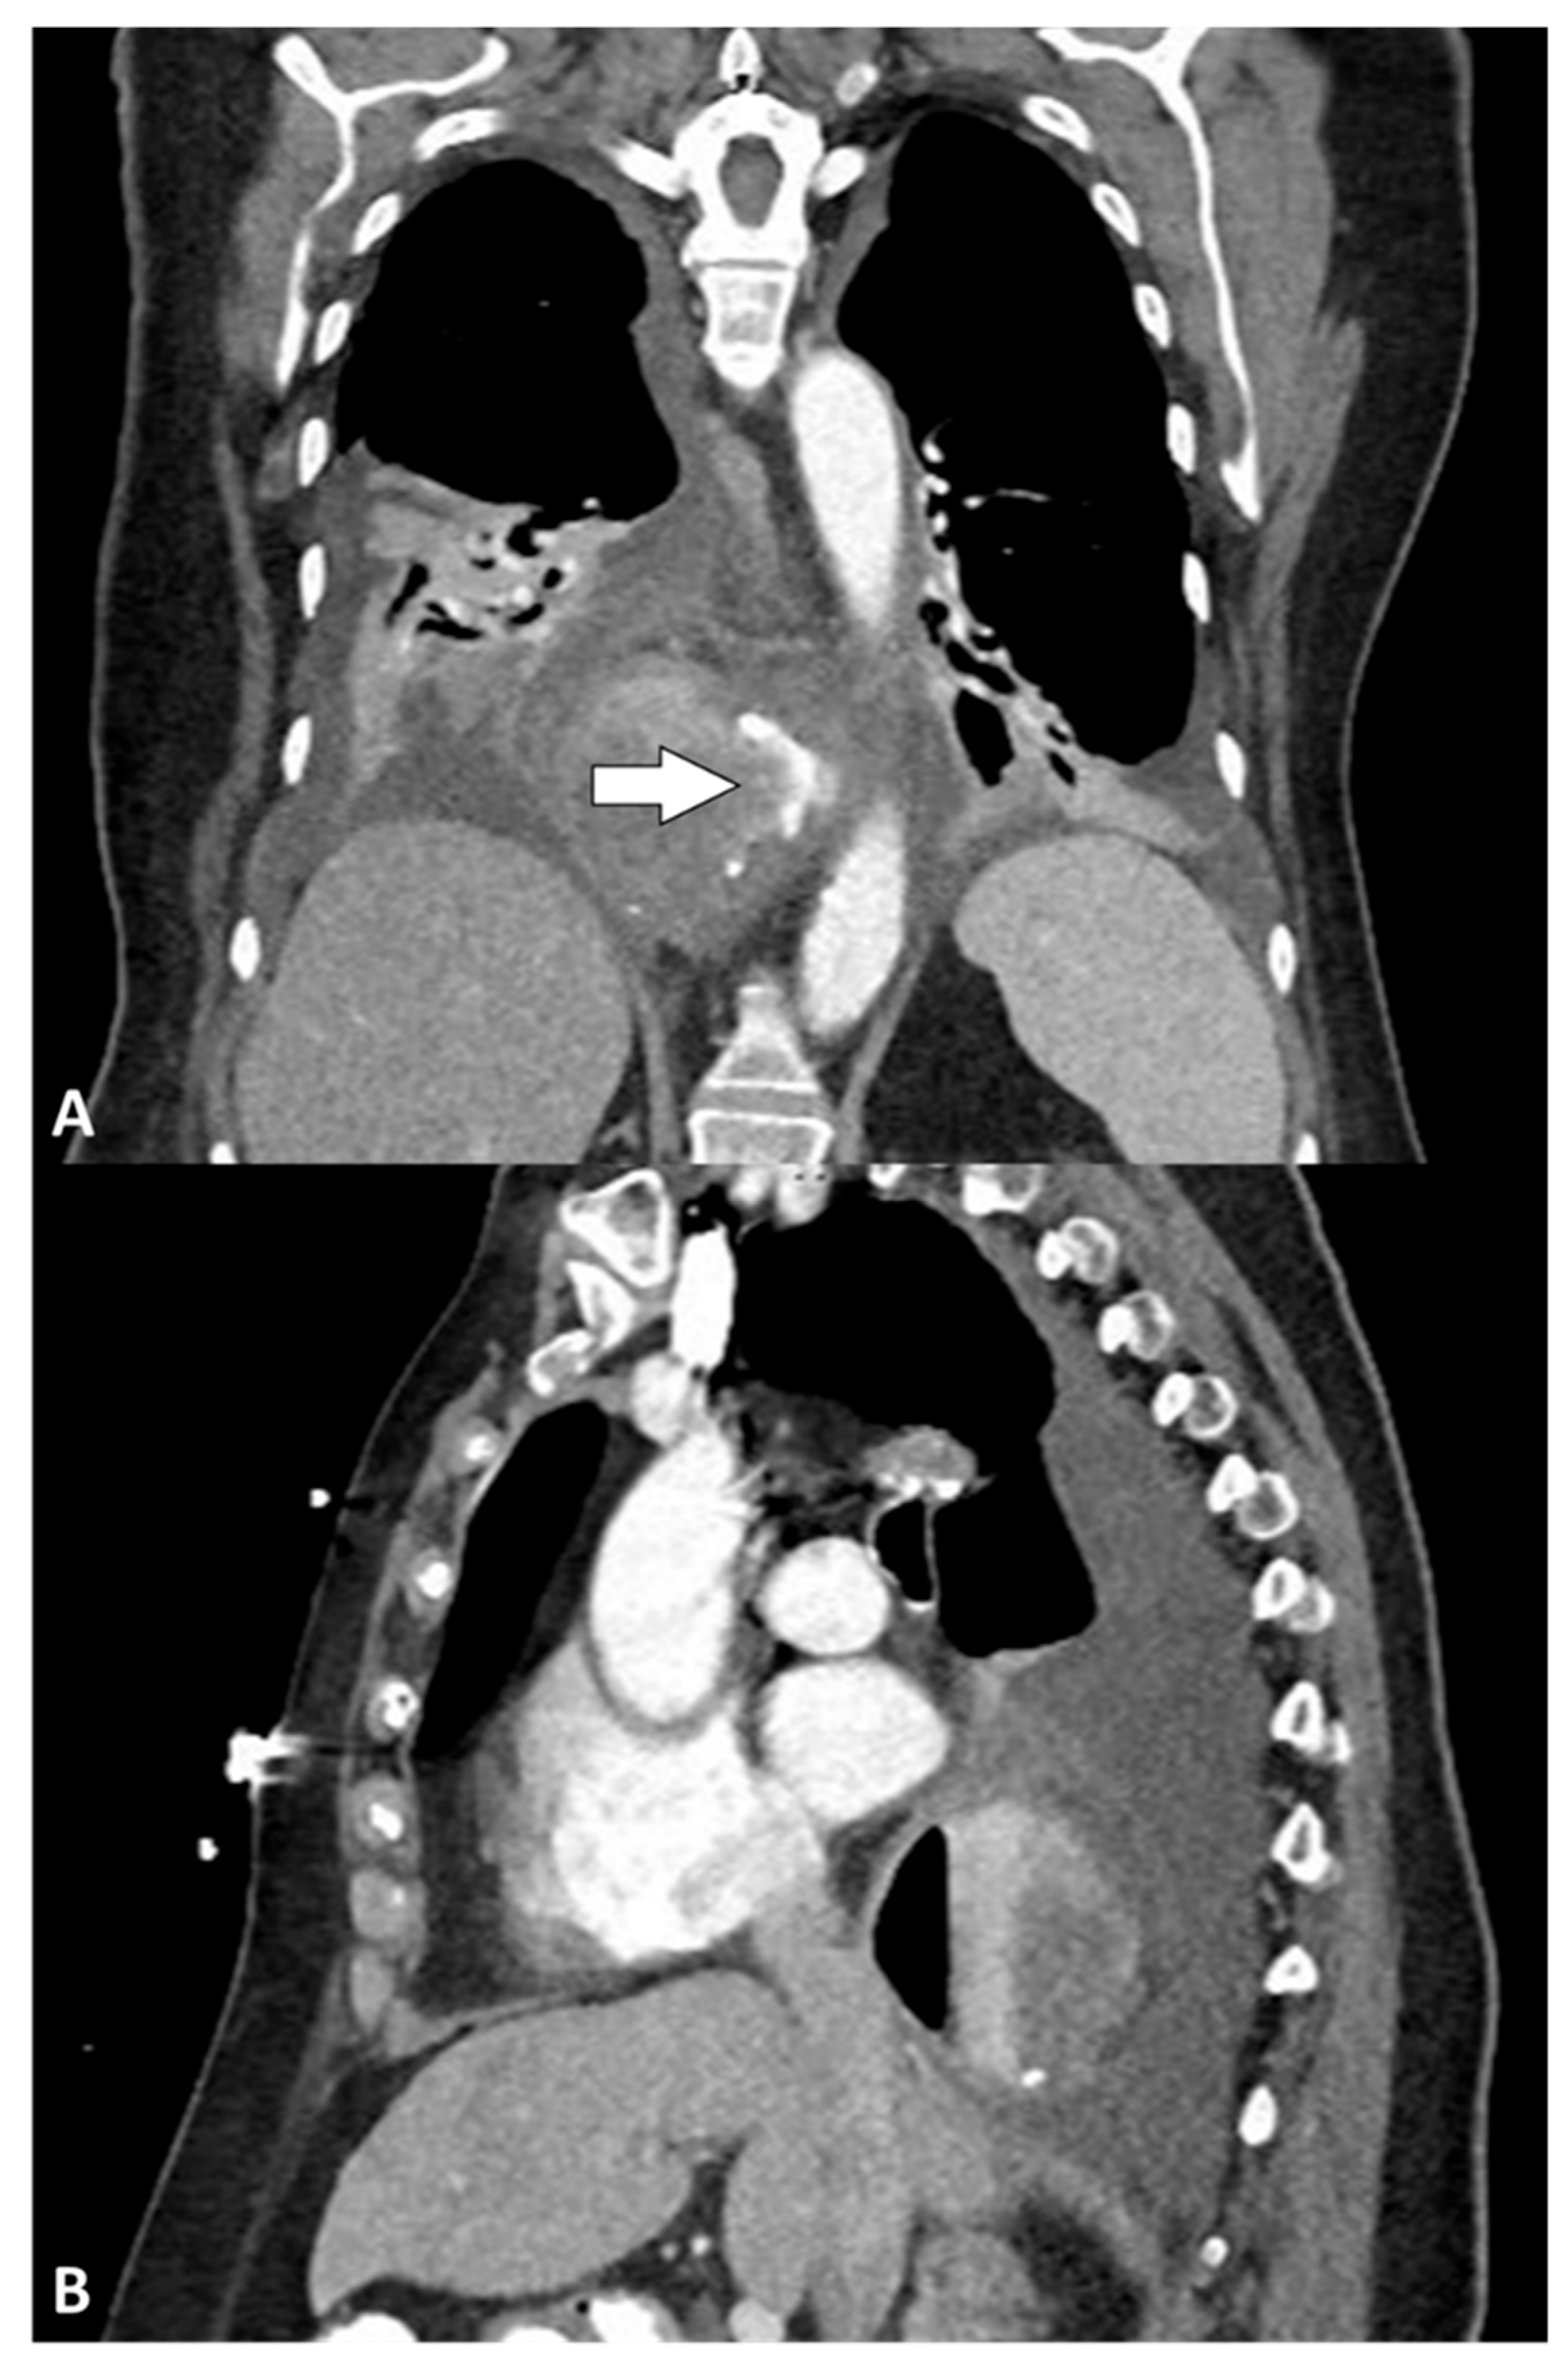

3.4. Perforation Treatment

| Computed tomography | 5 (100) |

| Contrast extravasation ** | 4 (80) |

| Pleural effusion | 5 (100) |

| Pneumomediastinum | 5 (100) |

| Pneumothorax | 3 (80) |

| Hiatal hernia recurrence | 2 (40) |